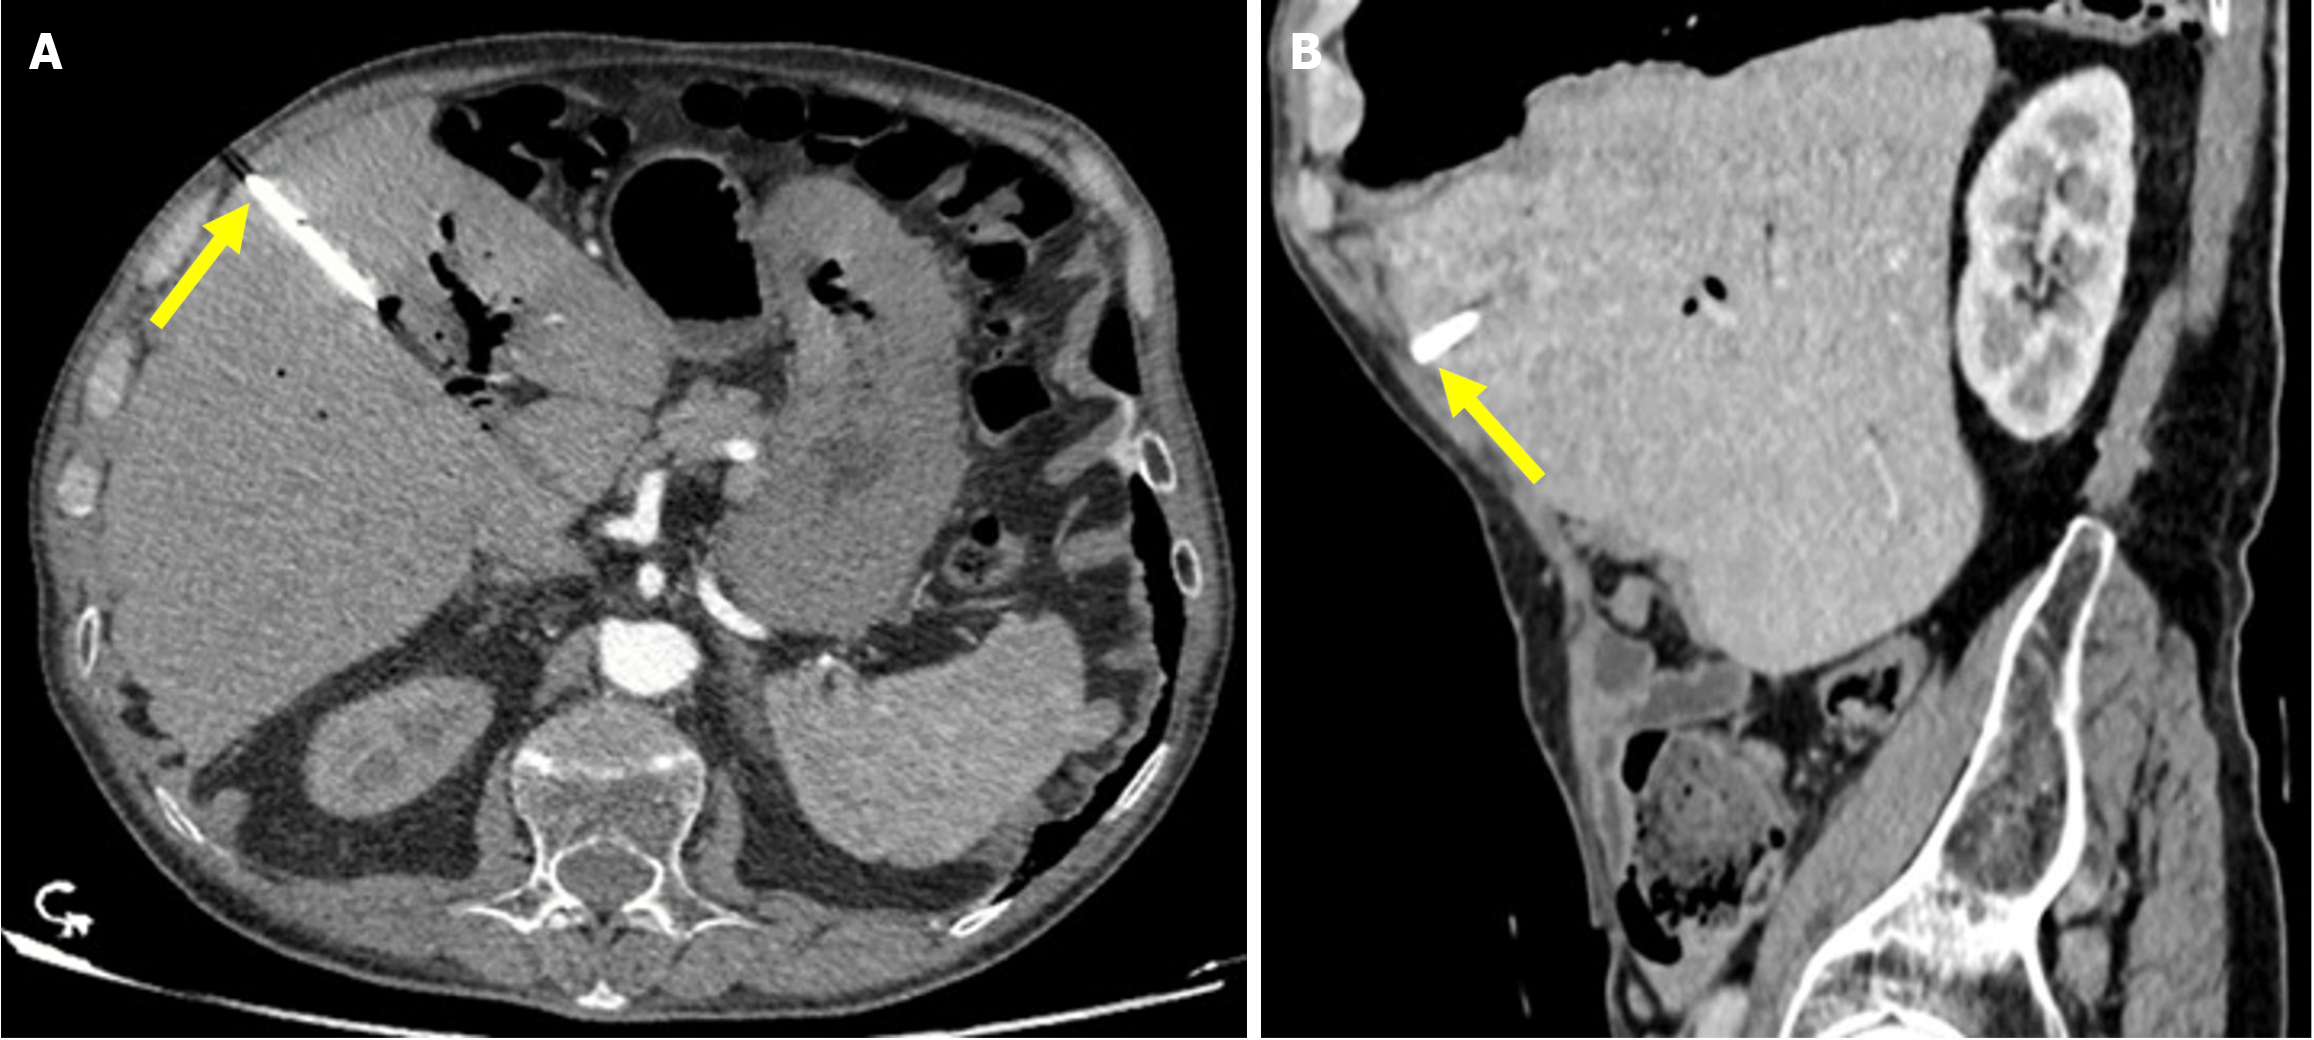

Imaging findings on US include a thick-walled, hydropic gallbladder, and pericholecystic fluid. Moreover, CT and MRI reveal abnormal gallbladder wall enhancement (Figure 7)[48].

Figure 7

Figure 7 Cholecystitis. A and B: Axial (A) and sagittal (B) contrast-enhanced computed tomography images showed findings consistent with post-endoscopic retrograde cholangiopancreatography cholecystitis in a 33-year-old female patient who presented 10 days after endoscopic retrograde cholangiopancreatography with abdominal pain, nausea, and a positive Murphy’s sign. The patient’s laboratory results revealed elevated levels of aspartate aminotransferase, alanine aminotransferase, and acute phase reactants. Imaging features included gallbladder wall thickening, increased mucosal enhancement (yellow arrows), and stranding in the pericholecystic fat (blue arrow).